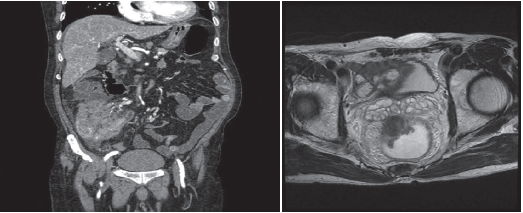

3. 자기공명영상(MRI)

MRI 검사는 CT검사에서 간 전이가 명확하지 않거나 간으로 전이된 암의 개수를 정확히 파악하고자 할 때 보조적으로 사용됩니다. 직장암 환자에서 시행하는 MRI의 경우, 직장 주변으로 암이 얼마나 퍼졌는지 알아보는데 유용하여 직장암 진단 후 치료 방침을 결정하는데 도움이 됩니다. CT검사와 다른 종류의 조영제 주사를 이용하므로 CT검사에서 사용되는 조영제에 부작용 반응을 보이는 경우에도 검사할 수 있습니다. 그러나 검사비가 비싸고, 검사 시간도 CT검사에 비해 길며, 좁은 원통형 공간에 들어가 검사를 하므로 폐쇄 공포증이 있는 경우에는 검사를 하기 어렵습니다.

[사진] MRI